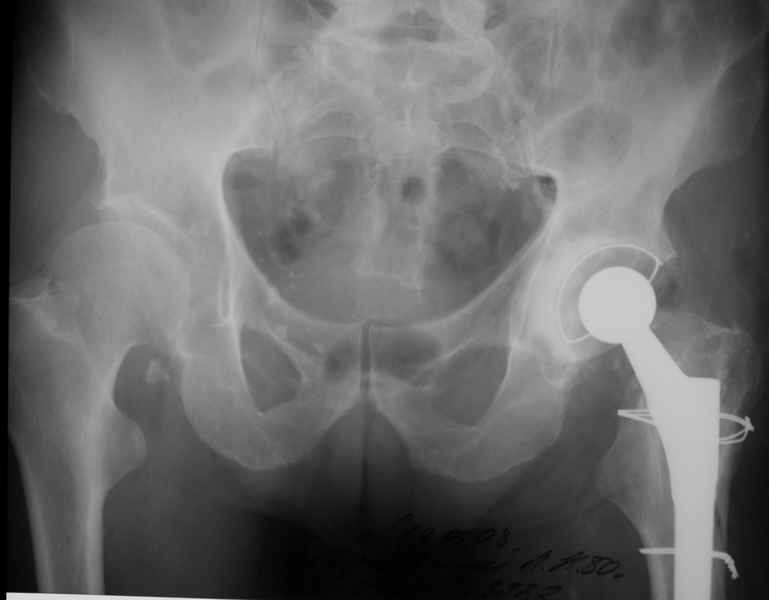

2. Применение ножки дистальной фиксации, мы отдаем предпочтение ножке Вагнера с фиксацией проксимального отдела на ножке. Более травматичное вмешательство, но при стабильной фиксации ножки реабилитация идет в обычном режиме.

Хочется показать два подобных случая, П-ка З. 72 лет и п-т Г. 80 лет. Сразу принимаю замечание, что это были ножки цементной фиксации, просто под руками не было бесцементника.

С уважением, Р.Тихилов